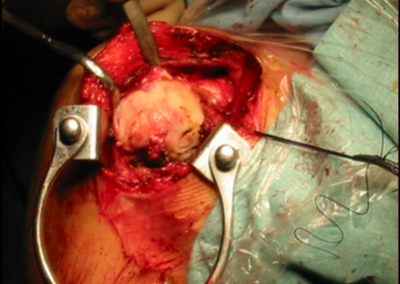

L’artropatia da rottura cronica e irreparabile della cuffia dei rotatori ha la sua espressione radiografica nella artrosi eccentrica dell’articolazione gleno-omerale (“acetabolarizzazione”):

a causa della perdita del centraggio della testa stessa legato alla insufficienza funzionale della cuffia